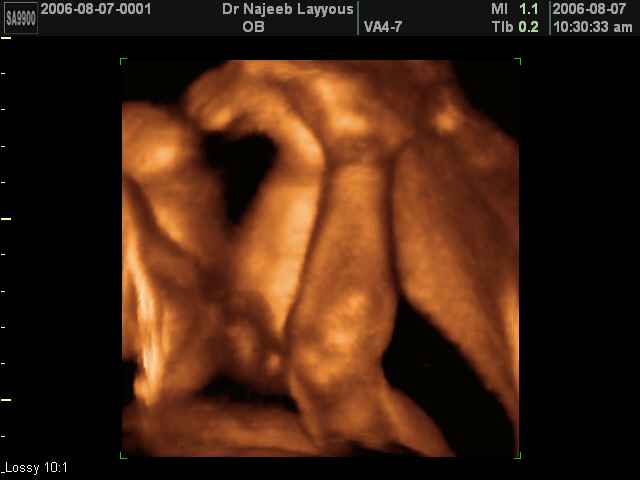

- تصرفات الجنين داخل الرحم

- صور لأطراف الجنين

- صور لتصرفات الجنين داخل الرحم

صور لأطراف الجنين بجهاز الالتراساوند ثلاثي الأبعاد | الدكتور نجيب ليوس